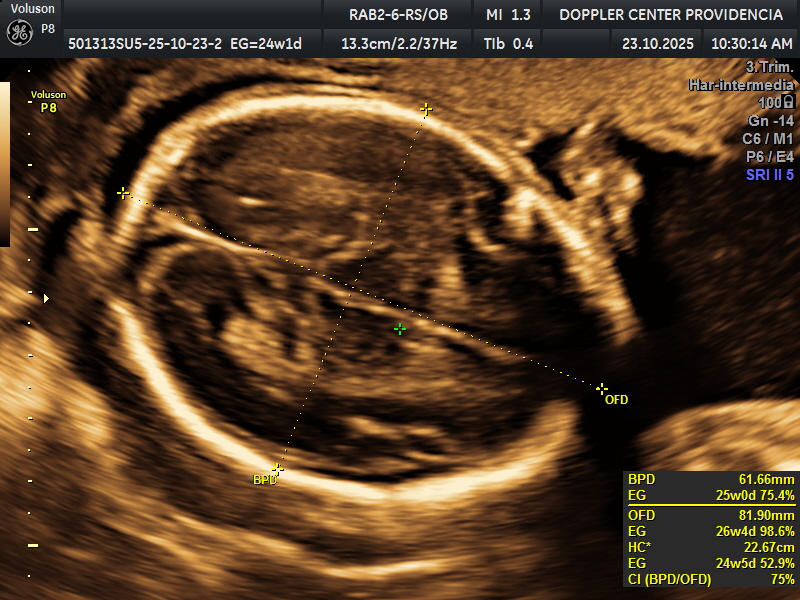

• Eco Doppler 22-24 semanas